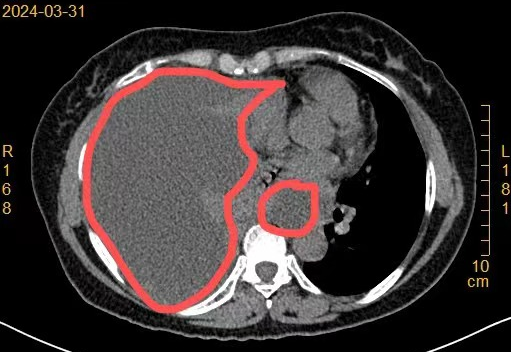

近半个月来,60岁的陈阿姨(化名)一直被咳嗽、气短、全身乏力和食欲不振所困扰,于是前往苏州九龙医院呼吸科门诊就诊。接诊的主任医师王军通过胸部CT检查,意外地发现了陈阿姨右侧存在大量胸腔积水,便安排她住院治疗。同时,呼吸内科也专门为此组织了一场专家讨论会。专家们一致认为应尽快为患者安排内科胸腔镜检查,以便更准确地诊断病因。

术中,采用“清醒镇静+局部麻醉”的方式,通过1cm小切口置入鞘管。内科胸腔镜进入胸腔后,发现胸腔内大量血性胸腔积液,壁层及脏层胸膜多发菜花状增生物。予以抽吸胸水后,用活检钳多部位夹取病变组织送检,进而为患者明确病因。